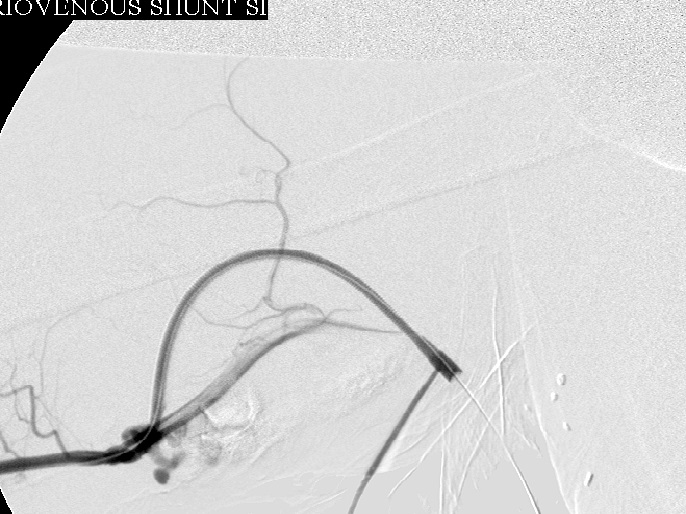

Right brachial arteriogram during intervention: Proximal brachial artery patent.